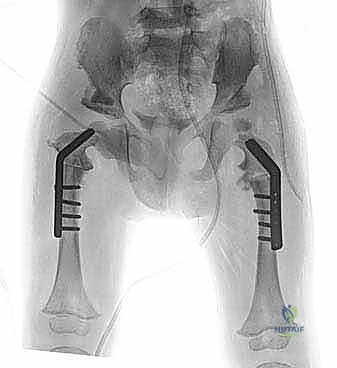

1. إجراء "السوبر هيب" (Superhip Procedure) وإصلاح الفخذ الأفحج

هذه هي الخطوة التأسيسية الأهم. لا يمكن تطويل عظمة الفخذ إذا كان مفصل الورك غير مستقر، وإلا سيؤدي التطويل إلى خلع المفصل.

* إصلاح الفخذ الأفحج (Coxa Vara Correction): يقوم الدكتور هطيف بقطع عظمي دقيق في أعلى الفخذ لتعديل الزاوية بين العنق والجسم، وتثبيتها بشرائح ومسامير خاصة بالأطفال. هذا يعيد الشد الطبيعي للعضلات المبعدة ويقضي على العرج.

* تحرير الأنسجة الرخوة: يتم إطالة الأوتار والعضلات المنكمشة التي تعيق حركة المفصل.

| المرحلة الثانية | 1.5 - 3 سنوات | جراحة "السوبر هيب"، قطع عظم الحوض (Dega)، إصلاح الفخذ الأفحج، وتصحيح تشوهات الركبة. | تثبيت مفاصل الورك والركبة لتتحمل قوى الشد أثناء التطويل المستقبلي. |

إحدى الحالات كانت لطفل يبلغ من العمر 4 سنوات، وُلد بفارق طول يتجاوز 7 سم مع عدم استقرار في مفصل الورك (Coxa Vara). بعد تقييم دقيق، أجرى الدكتور هطيف جراحة لإصلاح زاوية الفخذ وتثبيت الحوض. وبعد عام، خضع الطفل لعملية تطويل باستخدام جهاز إليزاروف. بفضل التزام الأهل بخطة العلاج الطبيعي والمتابعة الدورية في صنعاء، تمكن الطفل من المشي على قدمين متساويتين، وتخلص من العرج تماماً، وهو الآن يمارس رياضة كرة القدم مع أقرانه.